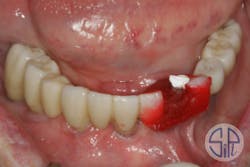

Following this verification step, a zirconia restoration was fabricated and delivered (figure 4). While screwing the restoration into place, a cracking sound was heard. The restoration had fractured lingually to the access hole of dental implant No. 27 (figure 5).

Figure 4: Newly delivered zirconia restoration

Figure 5: A fracture occurred in a lingual direction to the access hole of dental implant No. 27